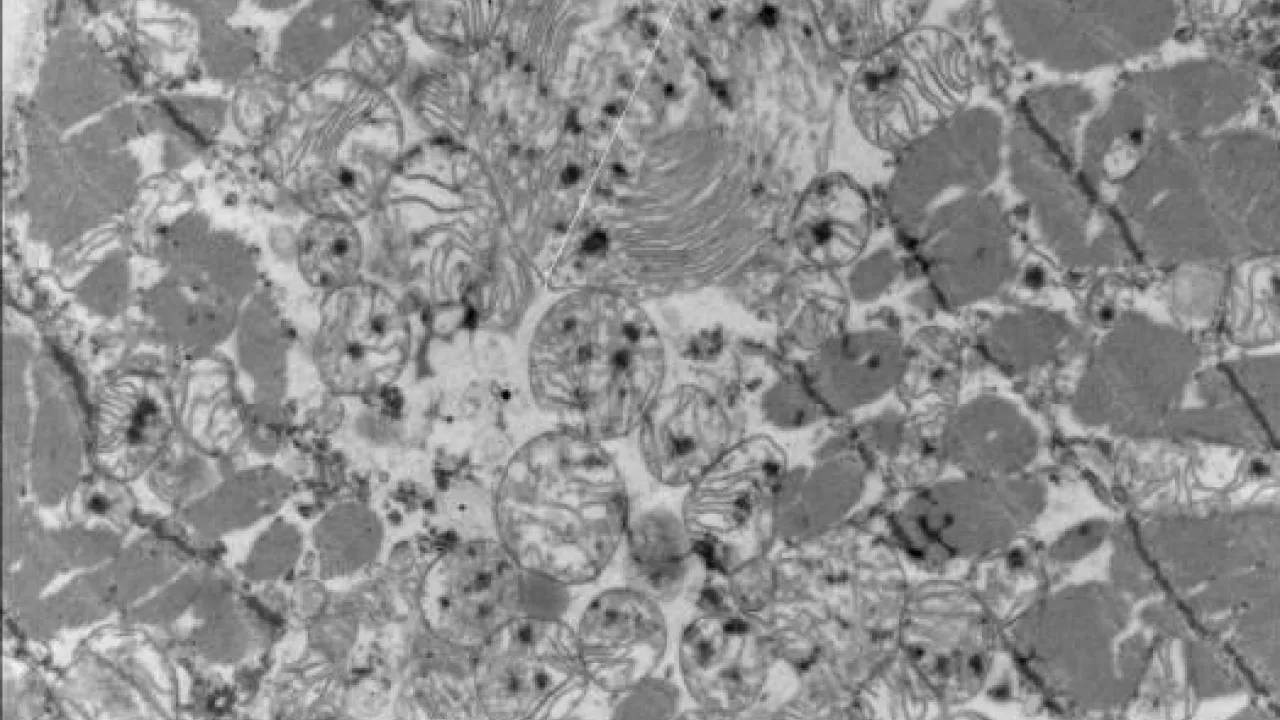

Heart, Leigh syndrome